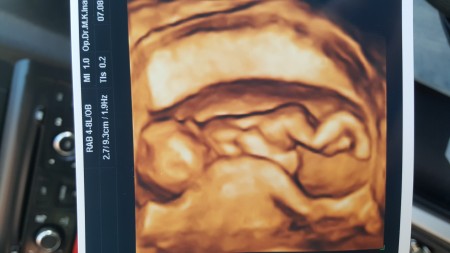

Bu 12+3 ultrason fotografimiz doktorum %80kız gibi emin degilim dedi sizler ne hissetiniz cok merak ediyorum

Ben daha yazıyı okumadan fotoğrafı görünce kız hissettim canım, :)

Ayyy masallah poposa bak ya cok tatli  sanki kiza benziyor gibi tez zamnda sag salim kucagina alirsin isallah;)))

Brdaki anne tecrubesi kimseyi doktor yapmiyo ama %80 kiz hissettim emin deglim :))